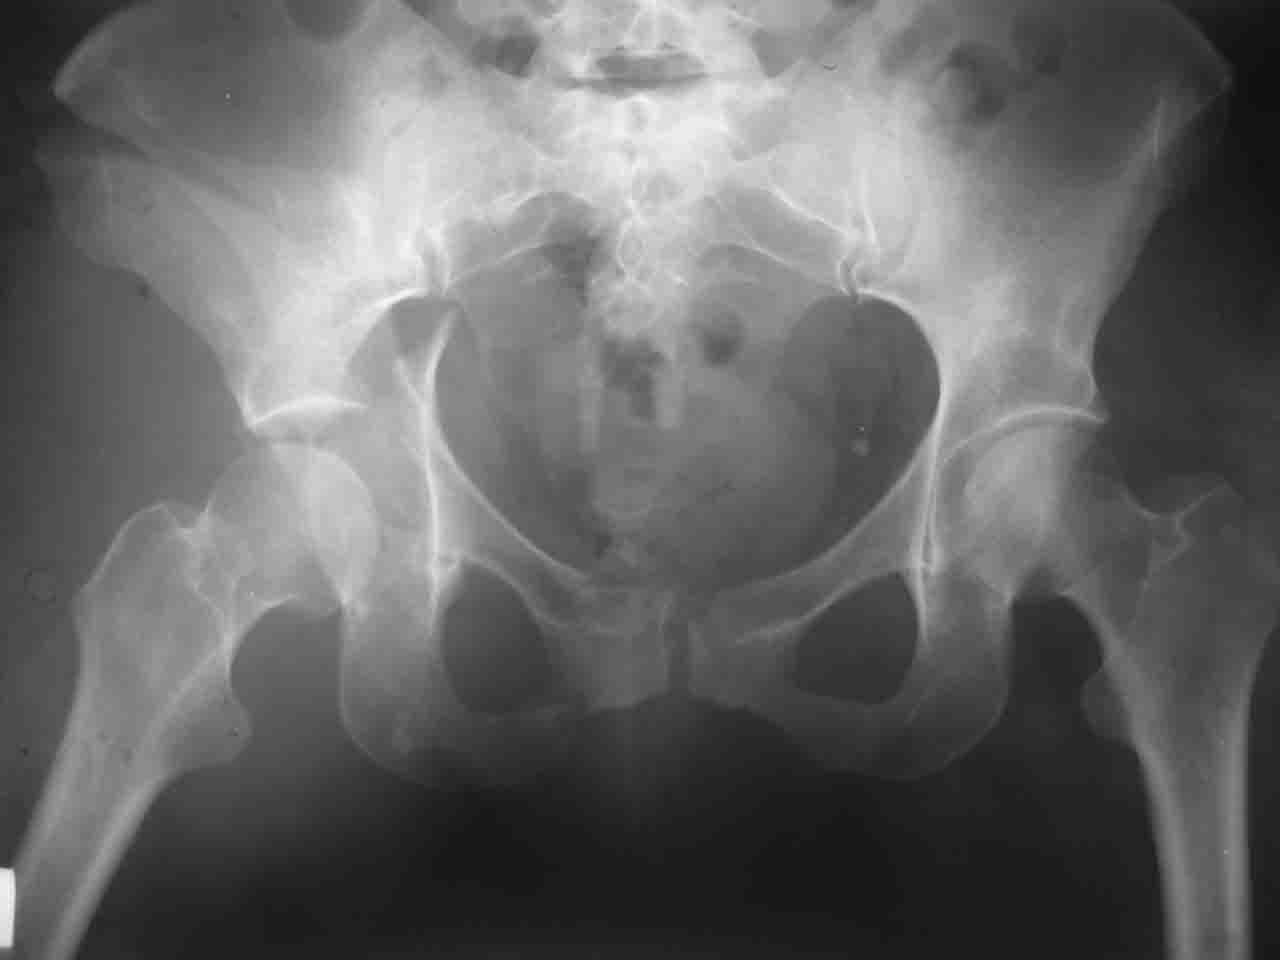

Логика подсказывает, что все-таки лучше иметь анатомически полноценную впадину, хотя ранее упоминалось состояние вторичной конгруэнтности и одно наблюдение у меня есть, когда у больного с полностью нарушенной анатомией впадины и подвывихом головки бедра кзади и кверху боли отсутствовали при относительно достаточном для стиля жизни больного объёме движений. Но это только одно наблюдение и кроме перелома впадины у этогобольного была и тяжелая ЧМТ в анамнезе. Основываясь на формулировке структуры ацетабулюм Э. Летурнеля - как перевернутой буквы Y, впадина для полноценной функции сустава должна иметь сферичность, соответствующую размеру головки бедра и если один из компонентов в дефиците, то функциональные последствия рано или поздно проявятся.

Сложностью, ассоциативностью характера перелома, я бы с радостью воспользовался мининвазивной перкутанной фиксацией винтами, но боюсь, что результат был бы ещё хуже, техникой непрямой репозиции перелома не владею, поэтому пытаясь получить анатомичную впадину приходится широко открывать, по крайней мере пока, а дальше буду пытаться уменьшать пространство...

> передним доступом на двухколонный перелом?

Илеофеморальный доступ не совсем передний и сравнительно с илеоингвинальным, и Кохера-Лангенбека открывает весь наружный таз кроме самых передних отделов лонных костей, фиксацию которых я не ставил в задачу. Обширность диссекции, большая длительность операции и более высокий риск гетерооссификации - отрицательные моменты в обмен на возможность легче ориентироваться.

Вопрос доступа к вертлужной впадине при остеосинтезе задача не простая. Конечно, у Летурнеля и Тайла всё давно описано, нам остается только брать на вооружение. Но сами понимаете, что не бывает двух одинаковых ситуаций, поэтому в каждом случае вопрос решается сугубо индивидуально. Наша главная цель - восстановить анатомию с нанесением минимальной дополнительной травмы тазобедреннному суставу, думаю с этим никто не поспорит. Расширенный илиофеморальный доступ уж слишком травматичен (как сказал один коллега "таз лежит отдельно, больной отдельно").Стоит ли делать из пациента анатомический препарат для того чтобы легче ориентироваться. Да и нужно ли собирать всю "мозаику"? Мы применяли при таких операциях своеобразную операционную хитрость - сначала устраняли грубое смещение крыла под гребнем с фиксацией так называемой "плавающей" пластиной (временно фиксированной на двух винтах)- доступ или продлевали боковой, или делали небольшой дополнительный разрез над гребнем. Это позволяло устранить грубое смещение и захождение отломков тела повздошной кости, что значительно облегчало репозицию и остеосинтез впадины над сводом. Основное внимание конечно же уделяли нагружаемому задне-верхнему отделу. Сообщите ваш адрес, пришлю схемы и рентгенограммы.